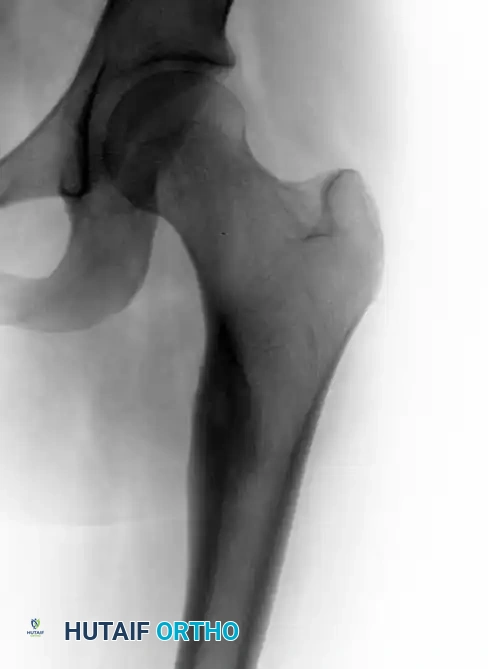

Anteroposterior view of the left hip in a 17-year-old girl complaining of left thigh pain, demonstrating a small radiolucent lesion with a thick sclerotic rim of reactive bone.

Standard orthogonal radiographs are often sufficient to establish the diagnosis, particularly in diaphyseal cortical lesions. The classic appearance is a small, radiolucent central nidus surrounded by a massive, thick rim of reactive sclerotic bone.

Plain Radiographs:

Imaging studies are usually definitive, and a biopsy is rarely required to confirm the diagnosis prior to definitive treatment. The diagnostic criteria hinge on identifying the central nidus, which by definition is less than 1.5 cm in diameter. Lesions identical in histology but larger than 1.5 cm are classified as osteoblastomas.